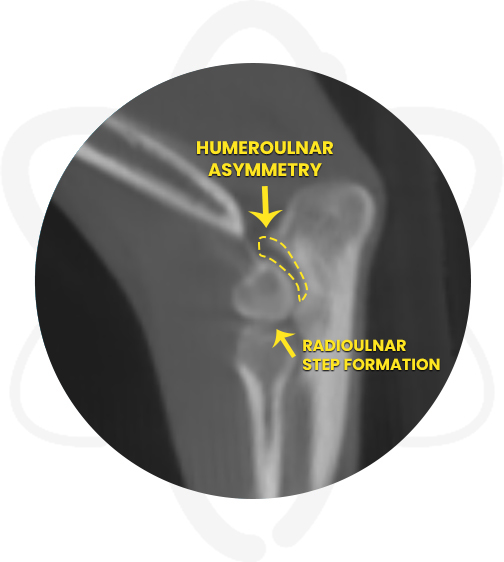

Patient is a 1 yr old, MN, Pomeranian that presented to orthopedic surgeon for evaluation of a grade II lameness (of weeks duration) affecting the right thoracic limb. Physical exam and radiographs revealed that the right elbow is not congruent when in flexion and the anconeus appears less dense and blunted. A CT scan of the elbows was requested to further evaluate the joints.

- Moderate complex joint incongruity right elbow joint and moderate subchondral bone sclerosis medial humeral condyle

- Provided the surgeon specific information regarding the suspected right elbow joint incongruency and determine the best treatment plan.